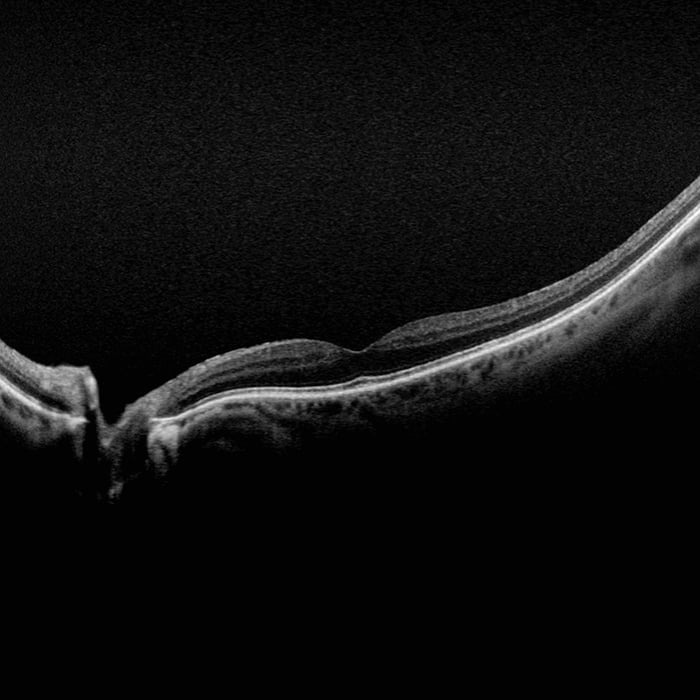

- Swept-Source OCT

- OCT: Querschnittaufnahmen okulärer Strukturen einschließlich des Fundus

- OCT: bis zu 23 mm Linien-Scan und Swept-Source Funktionaliät